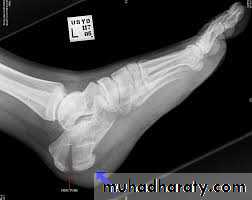

Calcaneal fracture, also known Don Juan fracture, is a fracture of the calcaneus. It is usually caused by a fall from height when one lands on their feet. These fractures represent approximately 2% of all fractures but 60% of tarsal bone fractures.